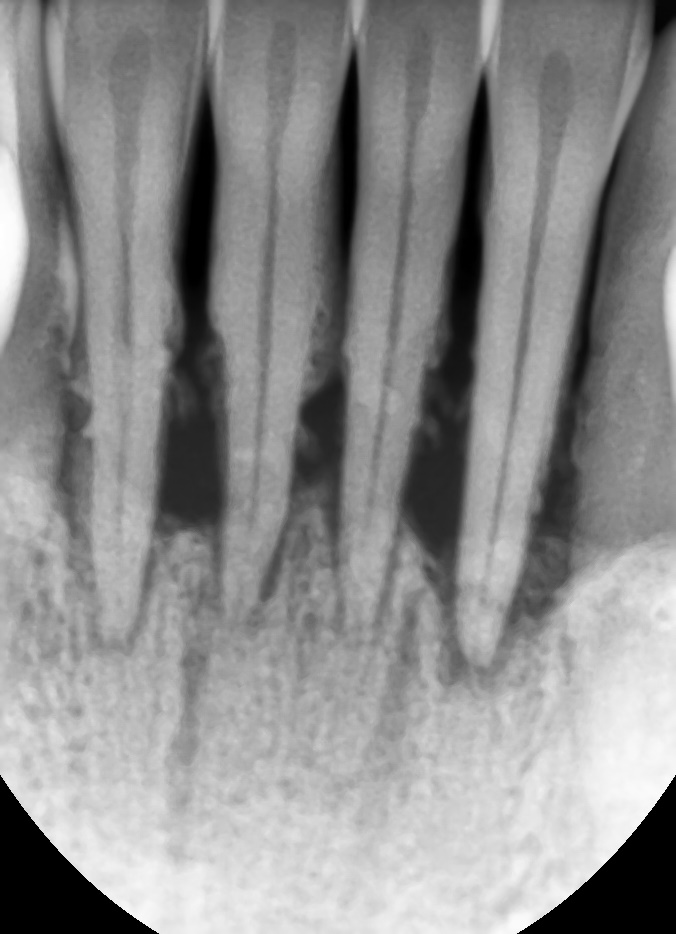

아래 앞니가 많이 흔들려서 내원하신 남성분

아래 사진을 보면 잇몸 속 치석이 아주 많고 이미 잇몸뼈가 거의다 소실되어 있습니다.